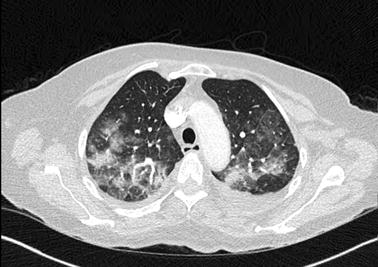

High-resolution computed tomography of the chest disclosed diffuse bilateral interstitial opacities with ground-glass shadowing, and pleural effusion bilaterally

Clinical features of 5-azacytidine-associated ILD include cough, dyspnea, pleuritic chest pain, and hypoxemic respiratory failure [2]. Like many antineoplastic agent-induced lung diseases, prominent imaging findings include diffuse multifocal ground-glass shadowing, interstitial thickening, and pleural effusion.